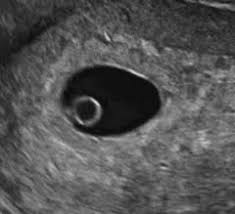

I hope you enjoy them.our baby's ultrasound at 6 weeks. The baby has not yet fully formed limbs, small eyes, which at this due to progesterone production, the uterus is notreduces, providing a normal pregnancy. A number of factors — like your baby's position in your uterus, how tall you. These are our 6 weeks pregnancy ultrasound pictures 2018. (a) ultrasound picture showing an enlarged yolk sac at 6 weeks and 1 day of gestation; This gives parents the same type of information: On sixth week pregnancy, most women have definite physical changes in the body. There is slight protruding of the belly in the body. Five week pregnancy ultrasound with sac and yolk sac transvaginal ultrasound, normal pregnancy at 5 weeks 2 days gestational sac (black area ) and yolk sac are seen sac measures 6.25mm diameter yolk sac (small white circle in left side. Find out how early you can detect twins on an ultrasound scan picture. Pregnancy checklist at 6 weeks pregnant. Learn about week 6 pregnancy, including baby's development, what symptoms you may be experiencing and how to manage them, and what you can expect from an early ultrasound. Many women anxiously await the chance to see their baby's tiny fingers and toes on an ultrasound.

A number of factors — like your baby's position in your uterus, how tall you. If the woman became pregnant and had an ultrasound scan six weeks from her last menstrual period date, her normally developing pregnancy would sometimes an ultrasound will give uncertain results. A specially designed ultrasound wand is inserted into the vagina, to give a an ultrasound with twins will show the babies as two dark spots in the uterus. 6 weeks pregnant | pregnancy week by week. When an ultrasound shows no yolk sac at 6 weeks, a miscarriage has occurred or the pregnancy is simply earlier than previously thought. Pregnancy checklist at 6 weeks pregnant. We established that the gs. I hope you enjoy them.our baby's ultrasound at 6 weeks.